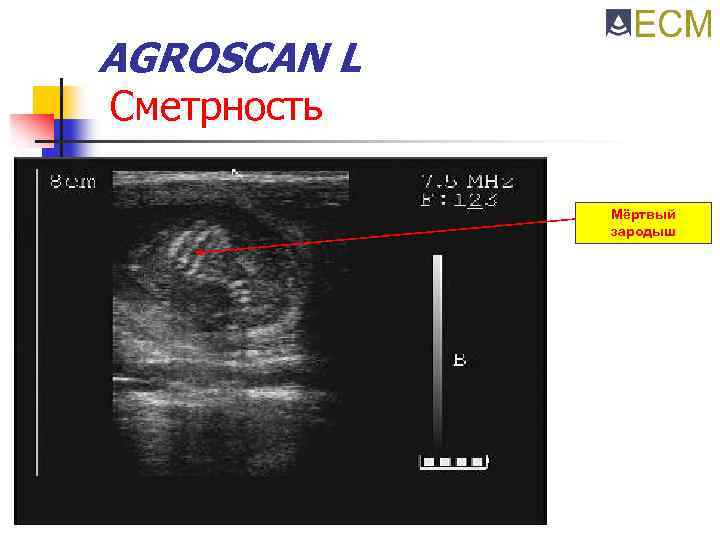

AGROSCAN L Сметрность Мёртвый зародыш